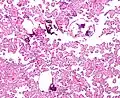

The tumor is neuroectodermal in origin and similar in structure to a normal choroid plexus. They may be created by epithelial cells of the choroid plexus. Papillary fronds lined by bland columnar epithelium are visible under the microscope. Normal absences include mitotic activity, nuclear pleomorphism, and necrosis.[10] Tumors have positive immunohistochemistry for cytokeratin, vimentin, podoplanin, and S-100.[11] Up to 20% of choroid plexus papilloma patients may test positive for glial fibrillary acidic protein (GFAP).[12] Studies have found that fourth ventricle cancers express more S100 than lateral ventricle tumors, and older patients (over 20 years) express more GFAP and transthyretin than younger patients.[13] Some individuals with choroid plexus papilloma have germline TP53 gene mutations, according to genetic analyses.[14] These cancers rarely exhibit nuclear p53 protein positivity. Aicardi syndrome, hypomelanosis of Ito, and 9p duplication are syndromic correlations of choroid plexus papilloma.

Plexuspapillom Detail -

Plexuspapillom Overview